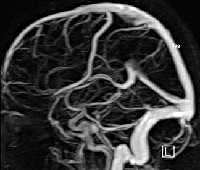

МРТ сосудов головного мозга

МРТ сосудов головного мозга. Диагностический метод для изучения строения сосудов головного мозга и характера кровотока. Этот метод позволяет визуализировать артерии, вены и венозные пазухи, чтобы оценить характеристики кровотока и его кровообращения в тканях мозга. В процессе МР ангиографии могут быть обнаружены компрессия, окклюзия, воспаление или нарушение целостности сосудистой стенки, порок развития, артериовенозный свищ, кровотечение. МРТ головного мозга не требует специальной подготовки. Перед контрастом оценивается функция почек и выявляется история аллергических реакций.

МРТ сосудов головного мозга основана на явлении ядерного магнитного резонанса. Суть его заключается в кратковременном колебании протонов ядер атомов водорода с образованием собственного магнитного поля, которое фиксируется аппаратом. Кровообращение в сосудах может значительно улучшить сигнал МРТ во внешнем магнитном поле. Это называется явлением импульсного потока (эффект). В радиологии существует два типа таких сигналов. Первый - это время полета, которое включает в себя эффект «улучшения потока в потоке» (эффект «притока») и эффект «потери сигнала» (нулевой поток), второй - фазовый контраст. Эти явления играют ключевую роль в исследовании кровеносных сосудов при церебральной ангиографии с помощью МРТ, поскольку они позволяют визуализировать сосудистое русло без дополнительного применения контрастных веществ. Этот метод широко используется в неврологии, нейрохирургии, травматологии и онкологии.